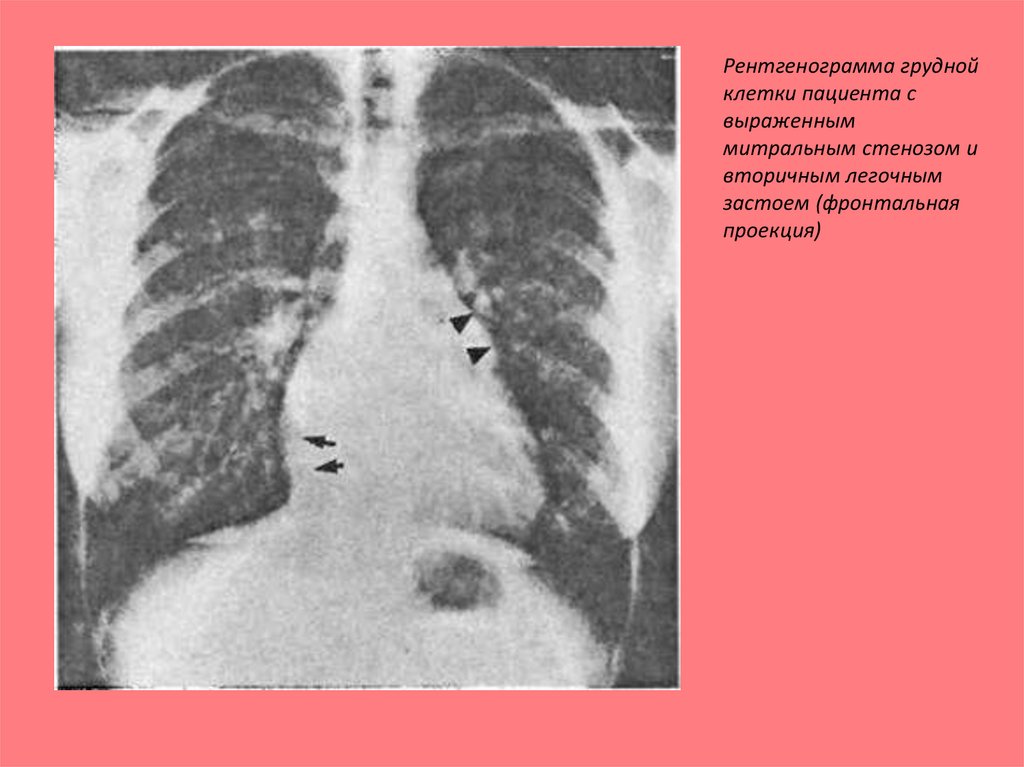

Рентгенограмма грудной

клетки пациента с

выраженным

митральным стенозом и

вторичным легочным

застоем (фронтальная

проекция)